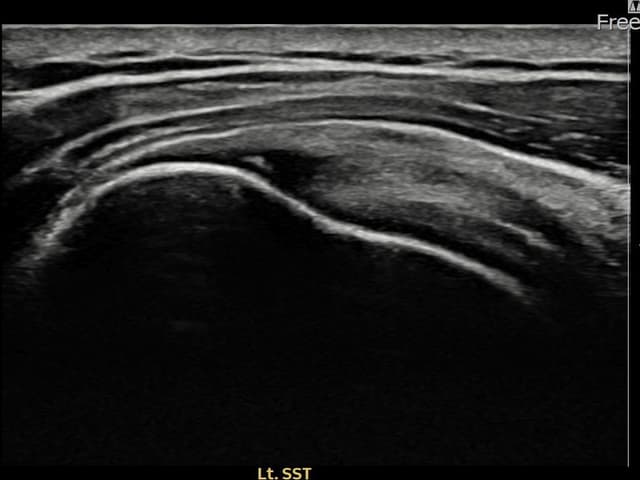

[経過期間: 23.07.31~23.09.27]

[縫縮術] 超音波検査にて左 棘上筋腱 부착부 광범위 部分断裂(13mm × 5mm (腱厚の約65%欠損))を確認。縫縮術施行後、腱の連続性が回復し、日常生活に復帰されました。